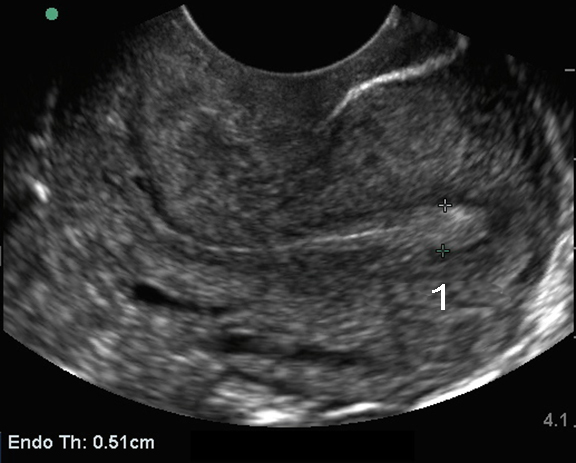

盆腔阴道内子宫:子宫内膜测量图像

子宫后倾

子宫内膜